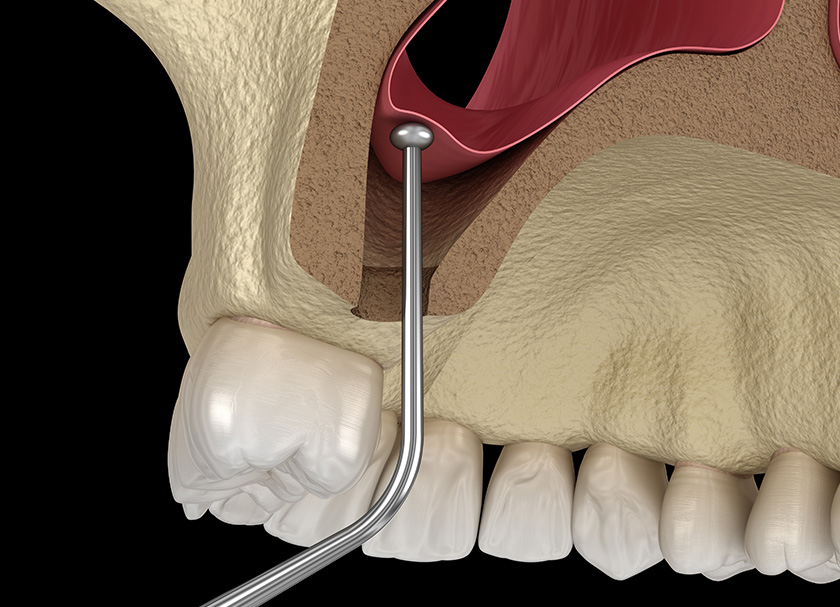

- The sinus membrane is raised through the implant osteotomy using gentle hydraulic pressure. This is done only in the region the implant is to be placed, thus making the procedure minimally invasive and leading to good, uneventful healing.

The perforation of the sinus membrane is the most frequent complication to worry about during sinus lift surgery. This risk is offset by taking proper scans and measurements during the planning phase, following a digitally guided approach, and using only gentle hydraulic pressure to raise the membrane. By not using sharp instruments in the surgical area, the risk of membrane puncture, and subsequent risk of chronic sinusitis and sinus infection are minimised.